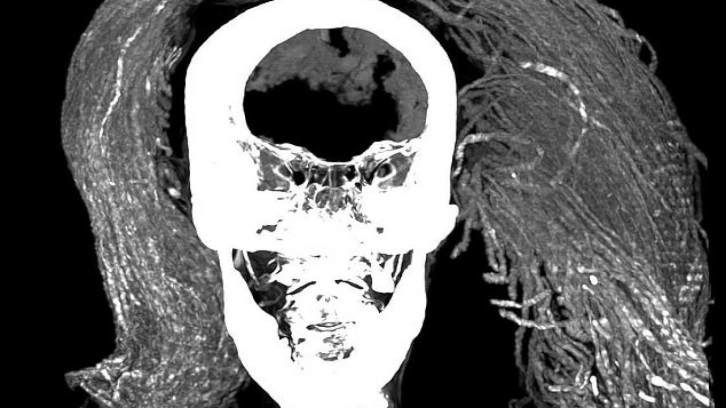

Frontiers in Medicine adlı hakemli dergide bugün (2 Ağustos) yayımlanan araştırmayı yürüten ekip, bilgisayarlı tomografi taraması ve X ışını kristalografisi gibi gelişmiş yöntemlerle kadının derisini, saçını ve peruğunu inceledi.

Bilim insanları kadının yaklaşık 1,55 metre boyunda olduğunu ve muhtemelen 48 yaşında öldüğünü tespit etti. Kadının ölüm nedeni saptanamadı ancak orta derecede artritten muzdarip olduğu bulundu.

Ayrıca mumyanın bütün iç organlarının yerinde durduğunu söyleyen araştırmacılar bunun alışmadık bir şey olduğunu ifade ediyor. Kahire Üniversitesi'nden çalışmanın ortak yazarı Dr. Sahar Saleem şöyle diyor:

Bu kanıtların özensiz bir mumyalama yapıldığı teorisiyle çeliştiğini söyleyen ekip, kadının ifadesinin nadir görülen, ani bir ölüm sertliği biçiminden kaynaklanabileceğini öne sürüyor.

Bilim insanları kadının ölümünden sonraki 18 ila 36 saat içinde, vücudu gevşemeden veya çürümeden önce mumyalanmış ve bu yüzden ağzının açık kalmış olabileceğini düşünüyor.

Dr. Saleem, "Açık ağzın, acılı bir ölüm ya da duygusal stresten kaynaklanabileceğini ve kadavra spazmının yüzünü ölüm anındaki görünümünde dondurduğunu öne sürüyoruz" diyerek ekliyor:

Mumyalama işlemini yapanların ağzı kapatamayıp kasılmış cesedi çürümeden ya da gevşemeden önce mumyalaması, ölümden sonra ağzın açık kalmasına yol açmış olabilir.